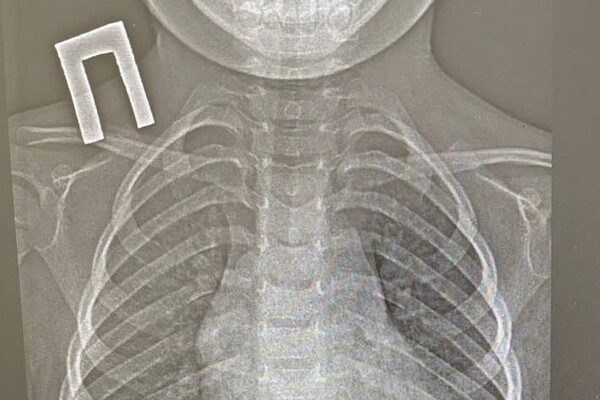

Пациенту провели рентген и обнаружили у него инородное тело в пищеводе, детский врач выполнил эндоскопическое удаление монетки. Вся процедура заняла около минуты.